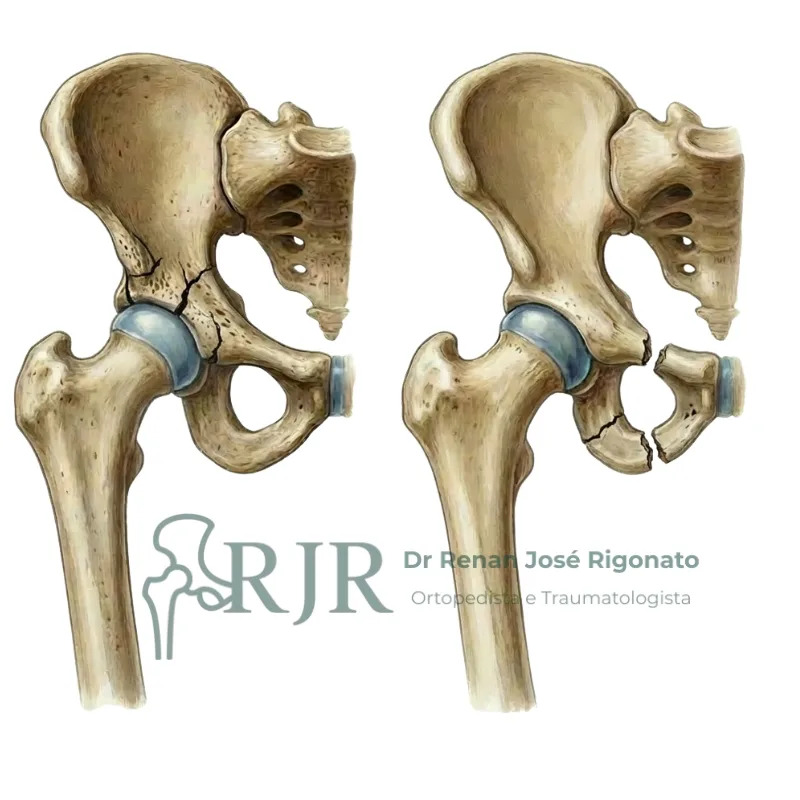

Fraturas da bacia

Lesões decorrentes de traumas de alta energia no acetábulo e anel pélvico. Exigem avaliação imediata.

Fraturas do fêmur

As fraturas do fêmur proximal acontecem principalmente no colo do fêmur e região transtrocanteriana. Ambas exigem tratamento imediato.